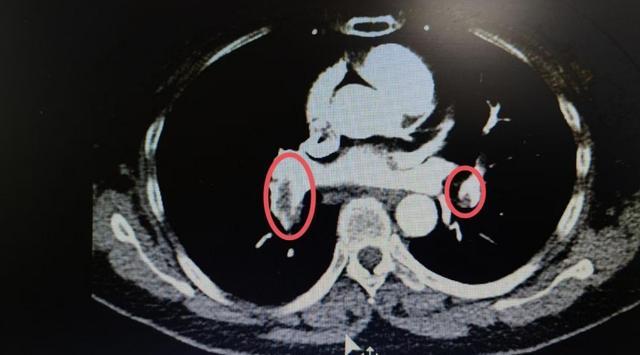

次日,患者未听劝导独自下床排便,突发一过性晕厥,口唇发绀,血压进行性下降,且诉胸部剧烈疼痛。医师予以紧急对症处理及完善相关检查,增强CT考虑是双下肺动脉主干及分支栓塞,立即转入重症医学科治疗。综合各专科专家意见,暂无需放置下腔静脉滤网,予以严密监护下溶栓治疗,未出现并发症,生命体征逐渐平稳。

(▲双下肺动脉主干及分支栓塞)